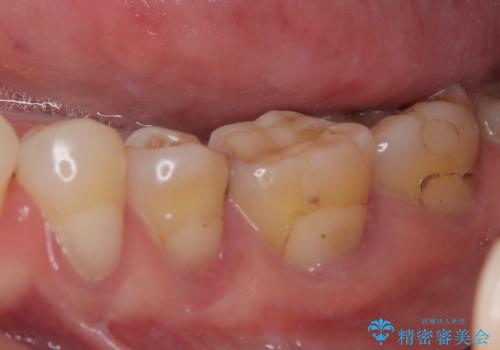

- 奥歯がたまにしみることがあるとのことで来院された患者様です。

特に問題となるような歯髄症状はなく、装着されている詰め物の境目がしみているような状態でした。

相談の上、フルジルコニアクラウンにて補綴治療を行うこととしました。